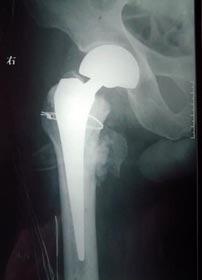

患者92岁,男性,股骨颈骨折,伴高血压、糖尿病、冠心病、骨质疏松。

采用小切口微创双极人工股骨头置换术置换术。

患者术后5天下地活动,恢复满意。